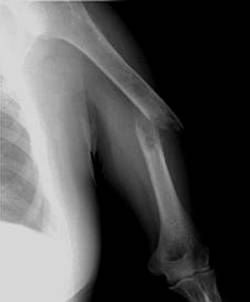

照片名称:左肱骨骨折